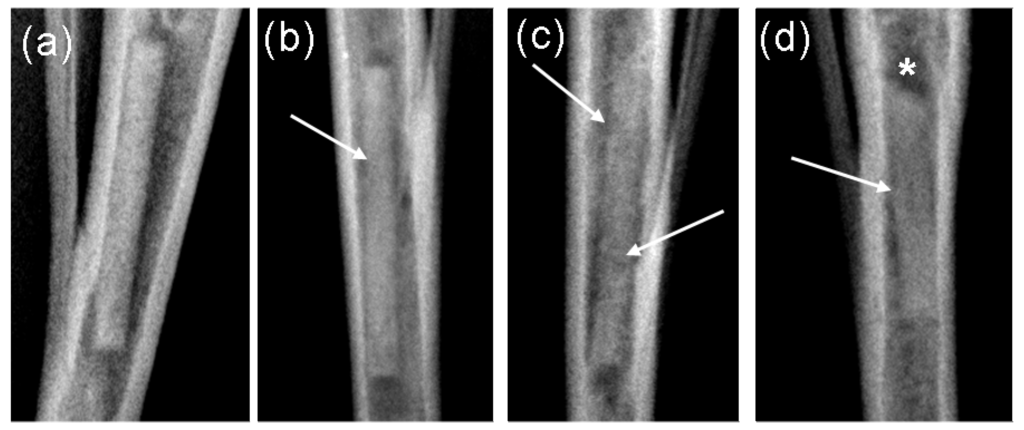

3.2.4. Radiological Investigation

Post operatively, the location of the implants was radiologically controlled. Digital x-ray images (Practix 160, Philips, Hamburg, Germany) of the tibiae were recorded weekly in the mediolateral and anterior-posterior beam path using 48 kV and 6.3 mAs. By means of the x-ray images, the appearance of the implants were assessed using semi-quantative scores [23] from 0 (no change), 1 (low structural loss of the implant without shape change), 2 (marked structural loss of the implant without shape change) and 3 (significant structural loss with shape change of the implant). Besides this, the occurrence of gas (low to high levels) was assessed on a computer (dicomPACS® vet Version 5.2.4; Oehm und Rehbein GmbH, Rostock, Germany) (Figure 12).

Figure 12.

Assessment of the implant’s degradation by means of anterior-posterior x-ray images: (a) Score 0: as on the day of implantation; (b) Score 1: low structural loss without shape change; (c) Score 2: marked structural loss without shape change; (d) Score 3; significant structural loss with shape change. Arrows indicate the structural loss, stars indicate shape changes.